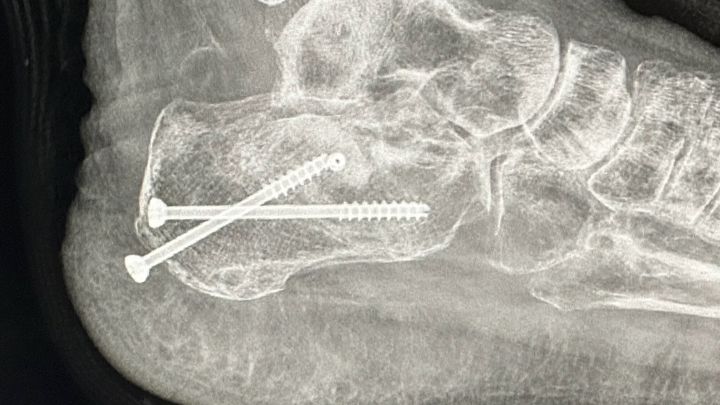

she's been working hard all her life but unfortunately a year and a half she had this unfortunately accident that she broke her heel bone in pieces she was ready to buy her dream house right before this accident happened now she spent all her savings in this situation and now she needs another surgery because the screws are coming out and she can potentially get the bone infected and high risk to get her foot amputate . . she cannot get social security and not disability because she worked with 1099 .. she needs help to keep up with rent and bills and she's terrified to get evicted most because she have two puppies that she needs to protect , and Plus she's been dealing with depression , she's in a good attitude and hope , from my heart thank you. Alma